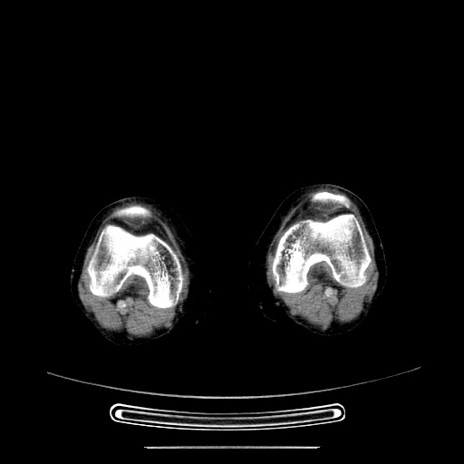

【症例】70歳代女性

【主訴】お腹が張る

【現病歴】1週間くらい前から腹部膨満の自覚あり。昨日夜から増悪したため、本日救急外来受診。

【身体所見】意識清明、BT 36.5℃、BP 165/106mmHg、HR 80bpm、SpO2 98%、腹部:膨満、軟、自発痛・圧痛なし、触診にて不快感あり、腸蠕動音:減弱

【データ】WBC 12600、CRP 1.04